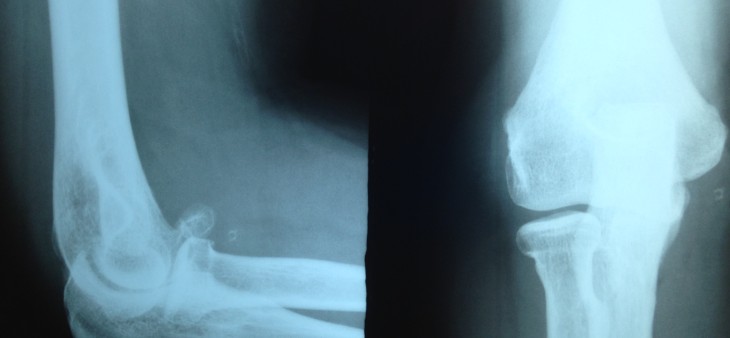

Artrofibrose ou Cotovelo Rígido

Doença que leva a diminuição do arco de movimento do cotovelo, normalmente secundária a uma lesão traumática, como fratura e/ou luxação em cotovelo, mas pode também estar associada ao tempo de imobilização da articulação, após tratamento cirúrgico de outras lesões e faz parte da evolução da osteoartrite. Diagnóstico é clinico e os exames de […]